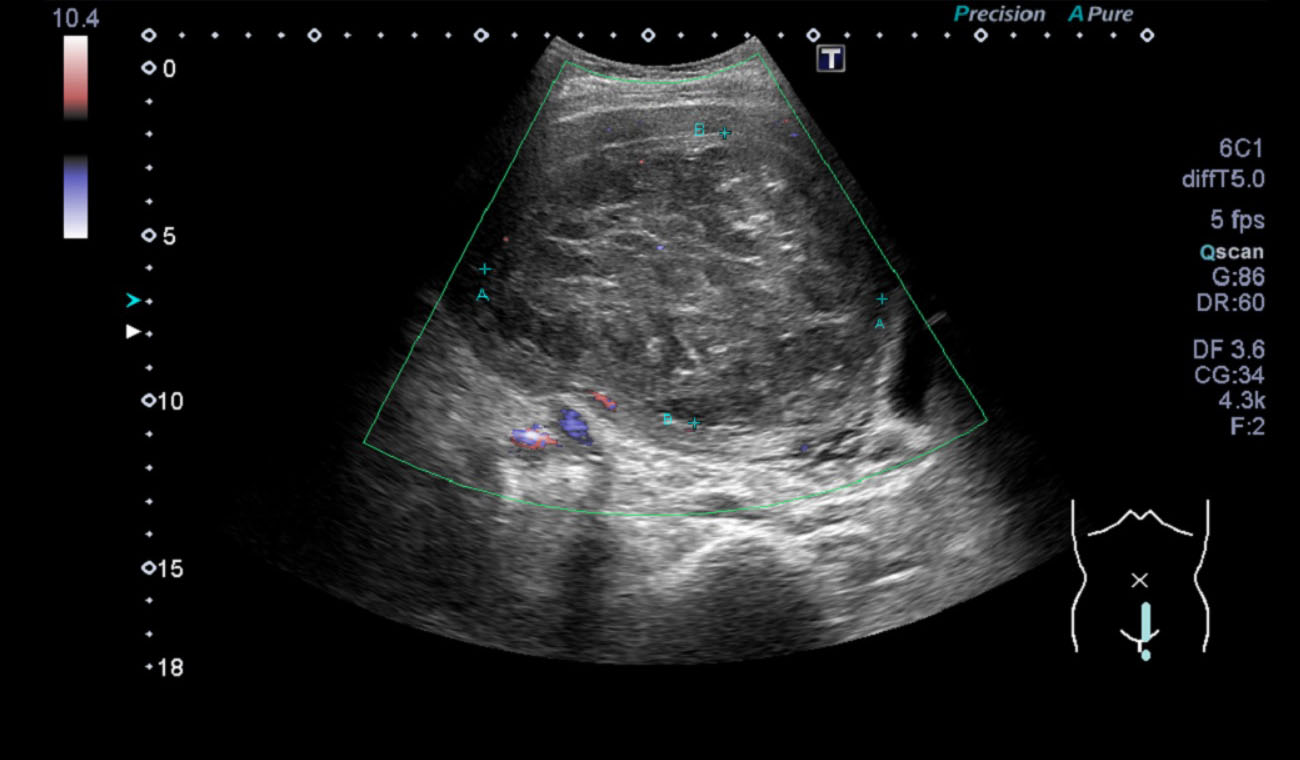

超音波(エコー) 診断画像

- 転移性肝がん

- 大腸がん

- 腎細胞がん